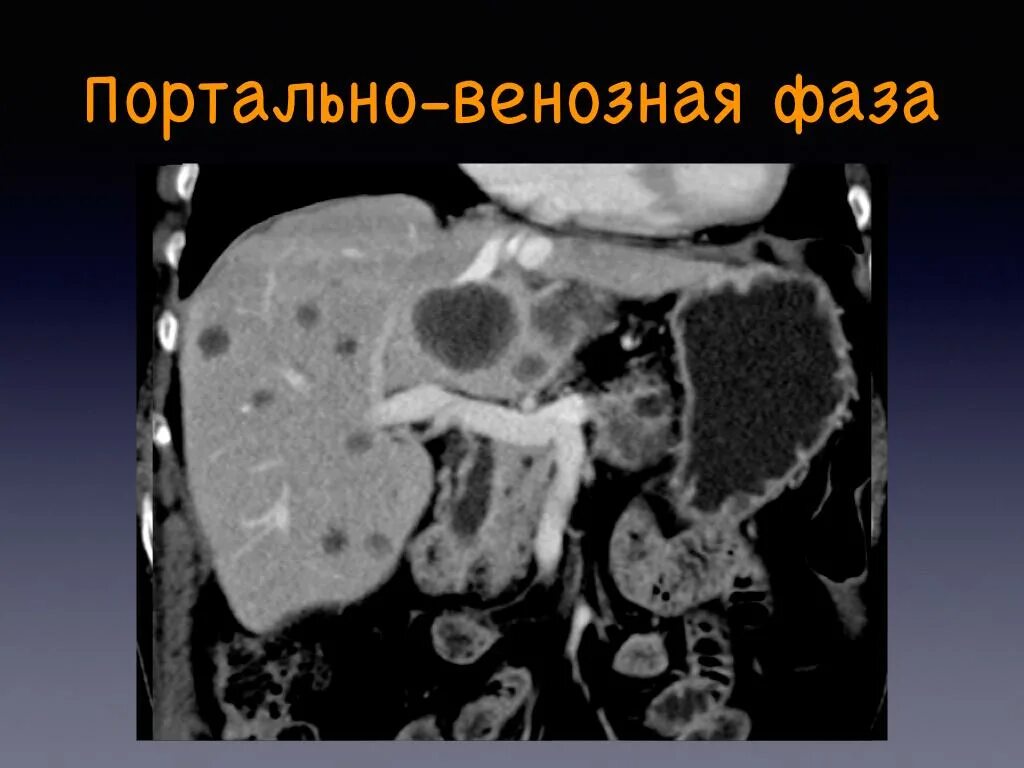

Фазы кт